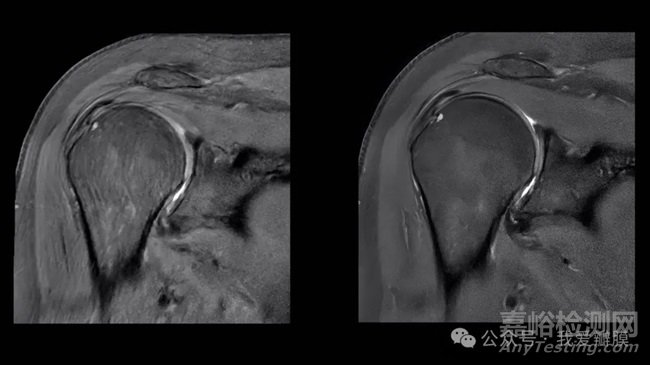

將肩部掃描(左)與使用 AI 功能銳化的相同圖像(右)進(jìn)行比較。Air Recon DL 是 GE Healthcare 的旗艦 AI 產(chǎn)品之一,旨在提高圖像質(zhì)量并縮短 MRI 掃描時(shí)間。

截至 2024 年 8 月 7 日,GE Healthcare 已獲得 81 臺(tái) AI 設(shè)備的授權(quán)。其旗艦 AI 產(chǎn)品之一 Air Recon DL 于 2020 年推出。GE Healthcare 的 AI 宣傳負(fù)責(zé)人 Jan Beger 表示,該算法可以提高圖像質(zhì)量并將 MRI 掃描時(shí)間縮短多達(dá) 50%。截至 10 月,該公司已使用該軟件掃描了超過(guò) 3400 萬(wàn)名患者。